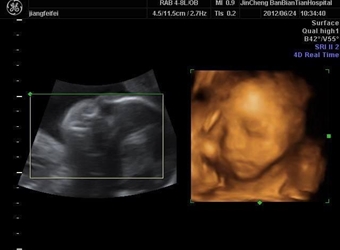

四维彩超是目前比较流行的孕检之一,四维能对胎儿头面部立体成像,可清晰显示胎儿的状态,网上很多四维是女孩但是却生了男孩的案例,那么四维女孩翻盘几率大吗…

四维彩超是实时的立体成像,在孕检的时候主要是帮助筛查胎儿的畸形,四维由于清晰度高也有用来判断胎儿男女,那么四维看是男孩有可能是女孩吗,四维男翻女的几…

四维彩超的报告中有很多的指标,网上也流传了很多通过报告单看男孩女孩的方法,那么四维胎儿双侧肾盂无分离是男是女,5个月四维如何看男女呢?更多关于生男生…

很多网上的宝妈都有看到这个情况,那就是做了四维彩超是男孩,但是却生了女孩,很多宝妈担心四维做的是男宝有可能翻盘吗,为什么四维男宝变女宝?更多关于生男…

网上有一种说法是,在做四维彩超的时候,如果是女宝宝是比较不容易配合的,如果是男宝宝更容易通过,那么是不是四维女宝更容易配合呢,四维女宝特征有哪些?更…

做四维彩超的时候,需要宝宝在肚子里动起来,有配合效果才是最好的,网上说做四维的时候不配合的都是女宝宝,那么这种说法是真的吗,四维是女宝还会翻盘吗?更…

很多宝妈都有在网上看到,做四维彩超的结果是女孩,但是最后生下的是男孩的案例,那么四维看是女孩最后会是男孩吗,女孩翻盘男孩的几率大不大?更多关于生男生…

网上流传着很多宝妈做四维彩超检查,医生说是男孩,但是结果生出来是女孩的案例,那么四维彩超男孩翻盘实例有哪些,为什么四维是男孩结果生女孩?更多关于生男…